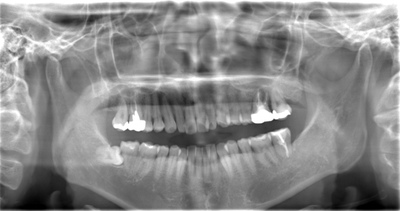

CASE 13

| 年齢・性別 | 32歳・男性 |

| 主訴 | 左上下の奥歯が痛い |

| 抜歯期間 | 60分 |

| 抜歯費用 | 約6,000円 別途CT撮影で3,000円 (2022年8月現在) |

| 抜歯内容 | 左上下の親知らず、左下7抜歯 |

| 治療方針 |

初診時は左上下の痛みでご来院されました。全体的に歯石を除去した後、主訴の解決のために虫歯が進行している左上下の親知らずと左下7の抜歯を行いました。 歯石除去と抜歯を行った後は、痛みが引いてきて口腔内の環境が変わったことに喜んでくれました。 今後は歯ぐきの状態を良くしながら、虫歯や欠損部の治療を行っていきます。 |